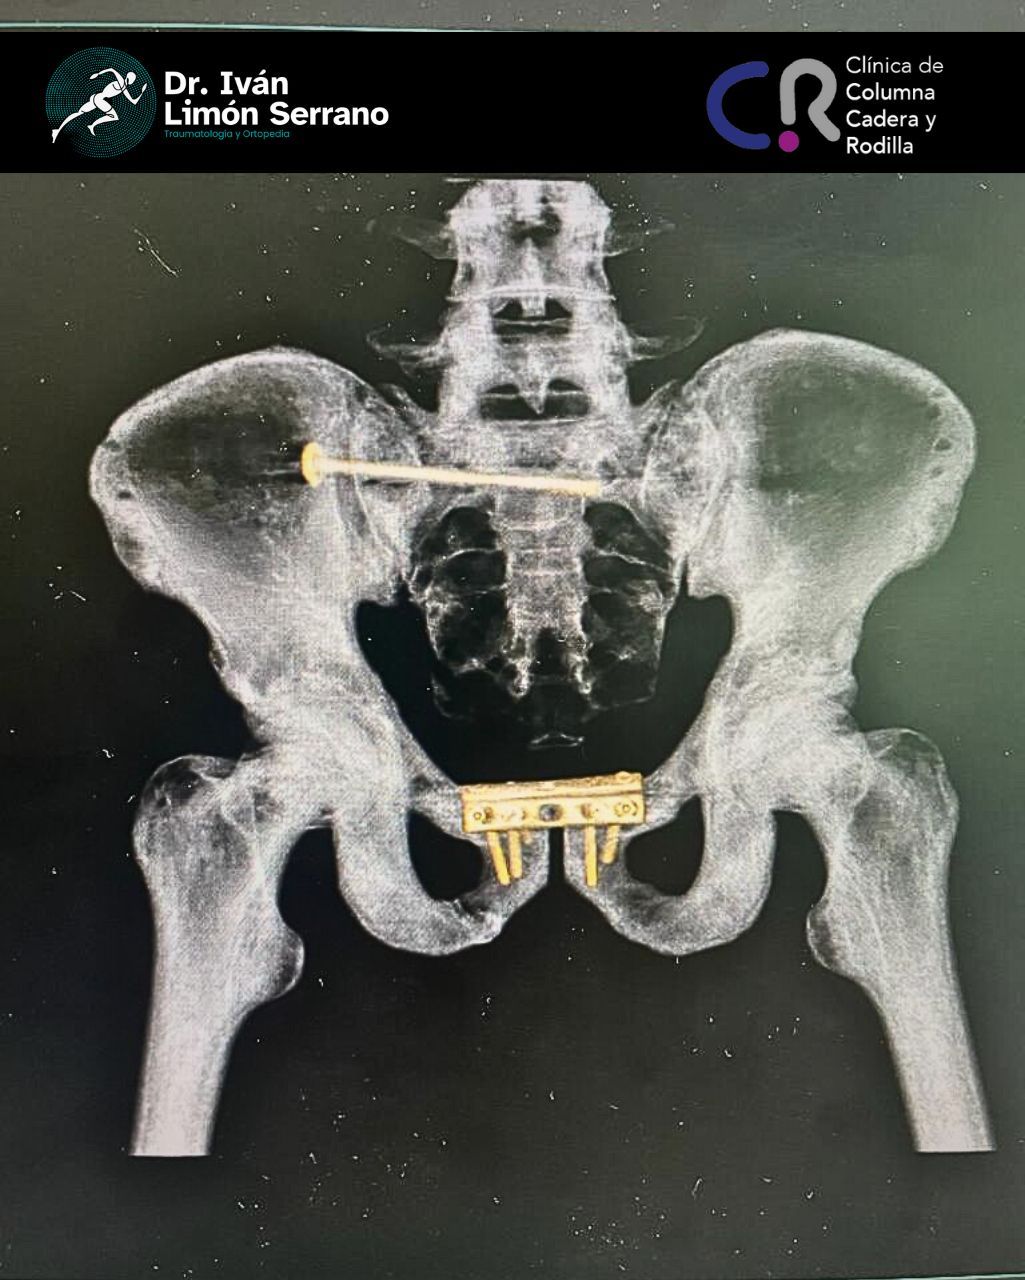

• Cirugía de columna

• Cirugía columna